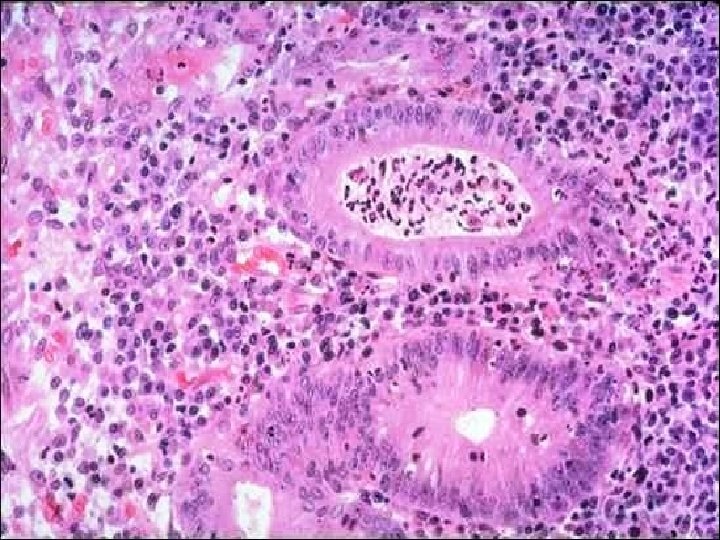

Microscopically, Crohn's disease is characterized by transnmural inflammation. Here, inflammatory cells extend from mucosa through submucosa and muscularis and appear as nodular infiltrates on the serosal surface with pale granulomatous centers.

At high magnification the Granulomatous nature of the inflammation of Crohn's disease is demonstrated here with epithelioid cells, giant cells, and many lymphocytes. Special stains for organisms are negative.